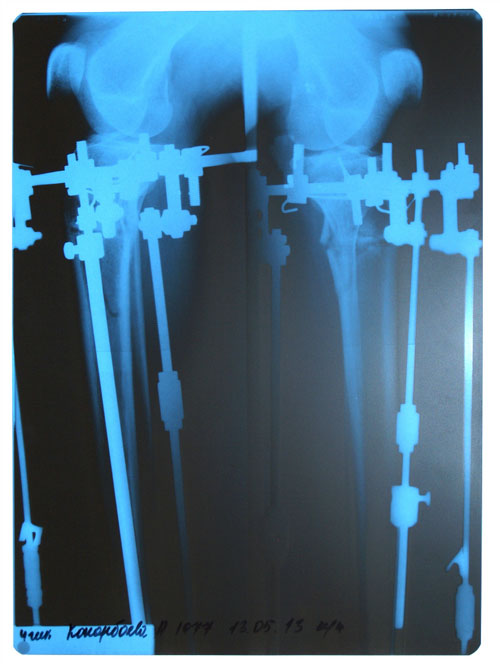

Рентгеновские снимки - 2 месяца с момента операции.

Здравствуйте, Sneginka! Ось ровная, сращение идёт хорошо! Продолжаем фиксацию.